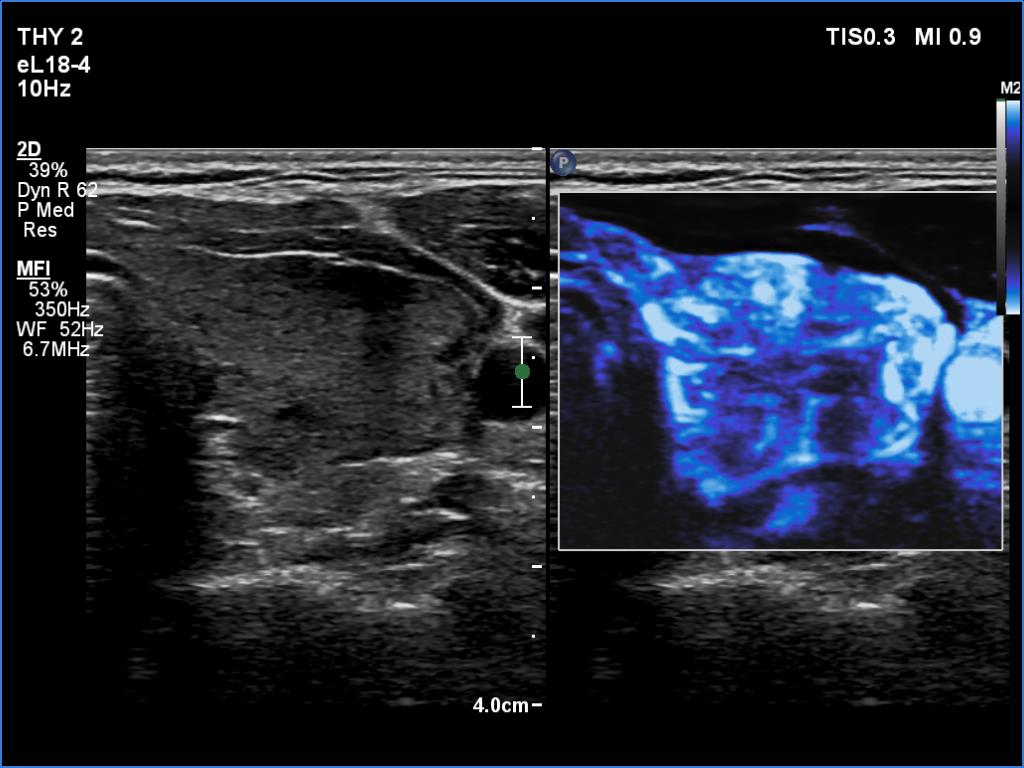

Graves' disease - case 799

Follow-up examination 9 months after the first visit (ultrasonographic picture 8)

Left lobe, transverse scan, microflow imaging.